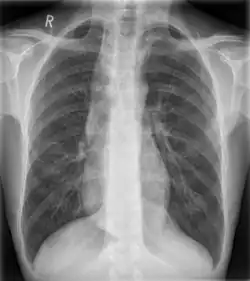

Some mediastinal structures on a chest radiograph.

Widened mediastinum/mediastinal widening is where the mediastinum has a width greater than 6 cm on an upright PA chest X-ray or 8 cm on supine AP chest film.[11]